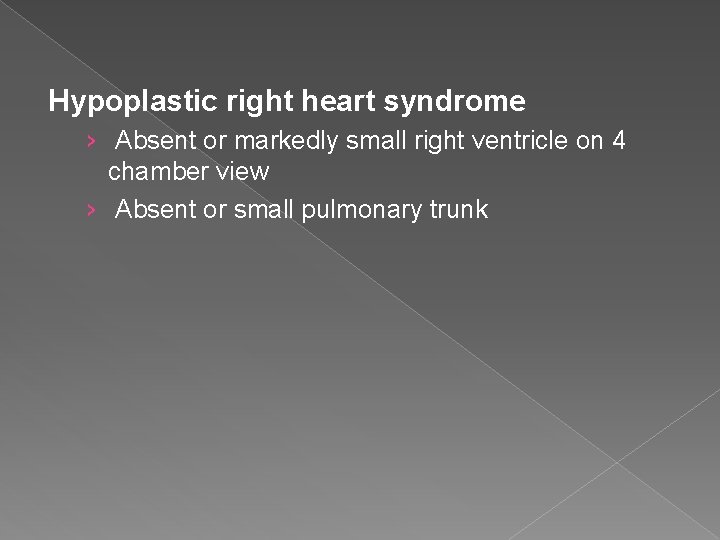

Hypoplastic Right Heart Syndrome � Generally occurs secondary to pulmonary atresia, with an intact interventricular septum. � Sonographic findings: � Absent or markedly small right ventricle on 4 chamber view � Absent or small pulmonary artery

Hypoplastic right heart syndrome › Absent or markedly small right ventricle on 4 chamber view › Absent or small pulmonary trunk